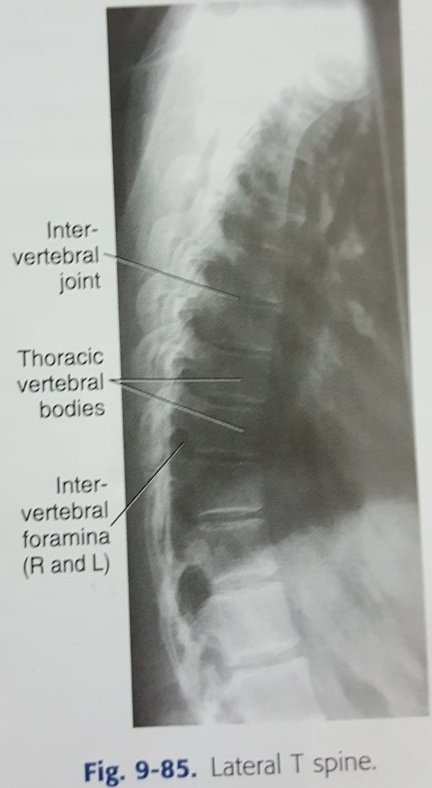

☆٤فحص الجانبي للفقرات الصدرية

Lateral view of thoracic spine

معلومات/

•الفقرات الصدرية عددها ١٢ فقرة.

•أهم فقرة هي الصدرية رقم ٧ ،لأنه يتم استخدامها كمركز للشعاع.

•يتم الاستدلال على موقعها بأنها تقع في منتصف المسافة التي تقسم عظمة القص (sternum) لجزأين متساويين.

من الأخطاء الشائعة في تصوير الفقرات الصدرية/

إهمال مسألة Anode heel effect

•عدم الطلب من المريض أخذ نفس عميق وطويل وبهدوء أثناء التصوير حتى نخفي تأثير الأضلاع.

الوضع:

على الطاولة ينام على جنب ويقوم بثني الركبتين و الورك ومد ذراعيه للأمام لمزيد من الثبات.

يكون الرأس باتجاه الأنود والقدمين باتجاه الكاثود (للتغلب على اختلاف الكثافة في الجسم بالاستفادة من Anode heel)

السنتر/

T7